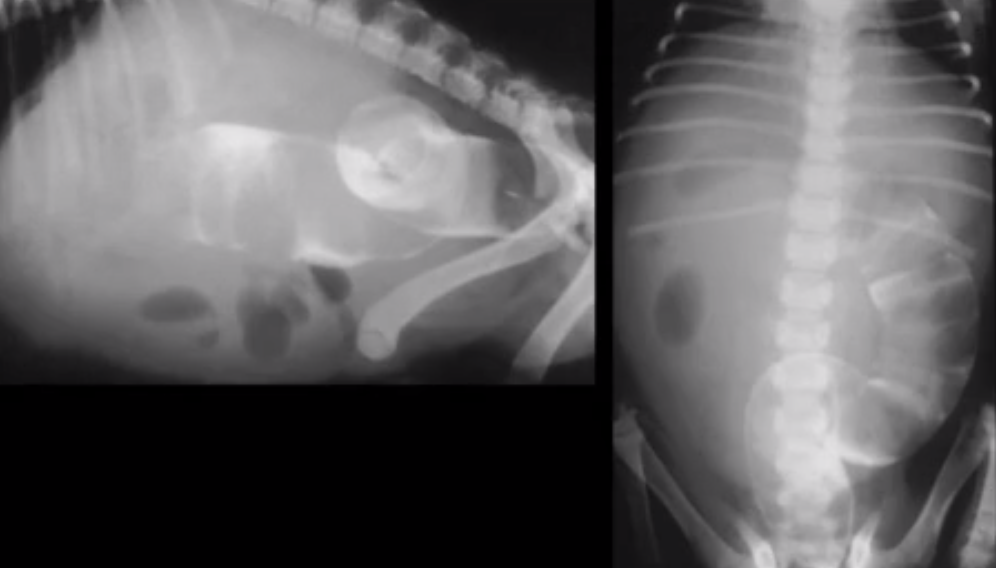

What does this image show?

Dilated uterus (no foetuses will be present until day 44)

General dilation

Ball FB with local dilation